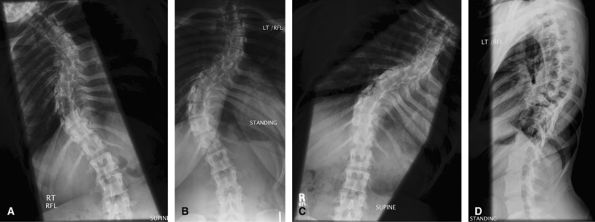

Scoliosis Series

Used to measure the Cobb angle and look for progression. Also used to look for underlying congenital vertebral anomaly.

Additional Views

Views taken erect, leaning to the left and to the right

are useful to look for mobile and fixed segments of scoliosis in

planning surgery.

![]() |

Figure 60 (A) AP best bend right. (B) AP erect. (C) AP best bend left.